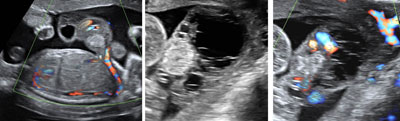

Pulmonic stenosis

Legend:Pulmonic stenosis: severe hypertrophy of right ventricle with little anterograde flow and regurgitation across the tricuspid valve; thickened and poorly opening pulmonary valve; streaming of flow into the pulmonary artery due to the combination of anterograde high velocity flow across the stenotic pulmonic valve and retrograde flow from the ductus venosus

Reference(s):Todros T, Paladini D, Chiappa E, Russo MG, Gaglioti P, Pacileo G, Cau MA, Martinelli P. Pulmonary stenosis and atresia with intact ventricular septum during prenatal life. Ultrasound Obstet Gynecol 2003;21(3):228–33. PubMed PMID: 12666215.